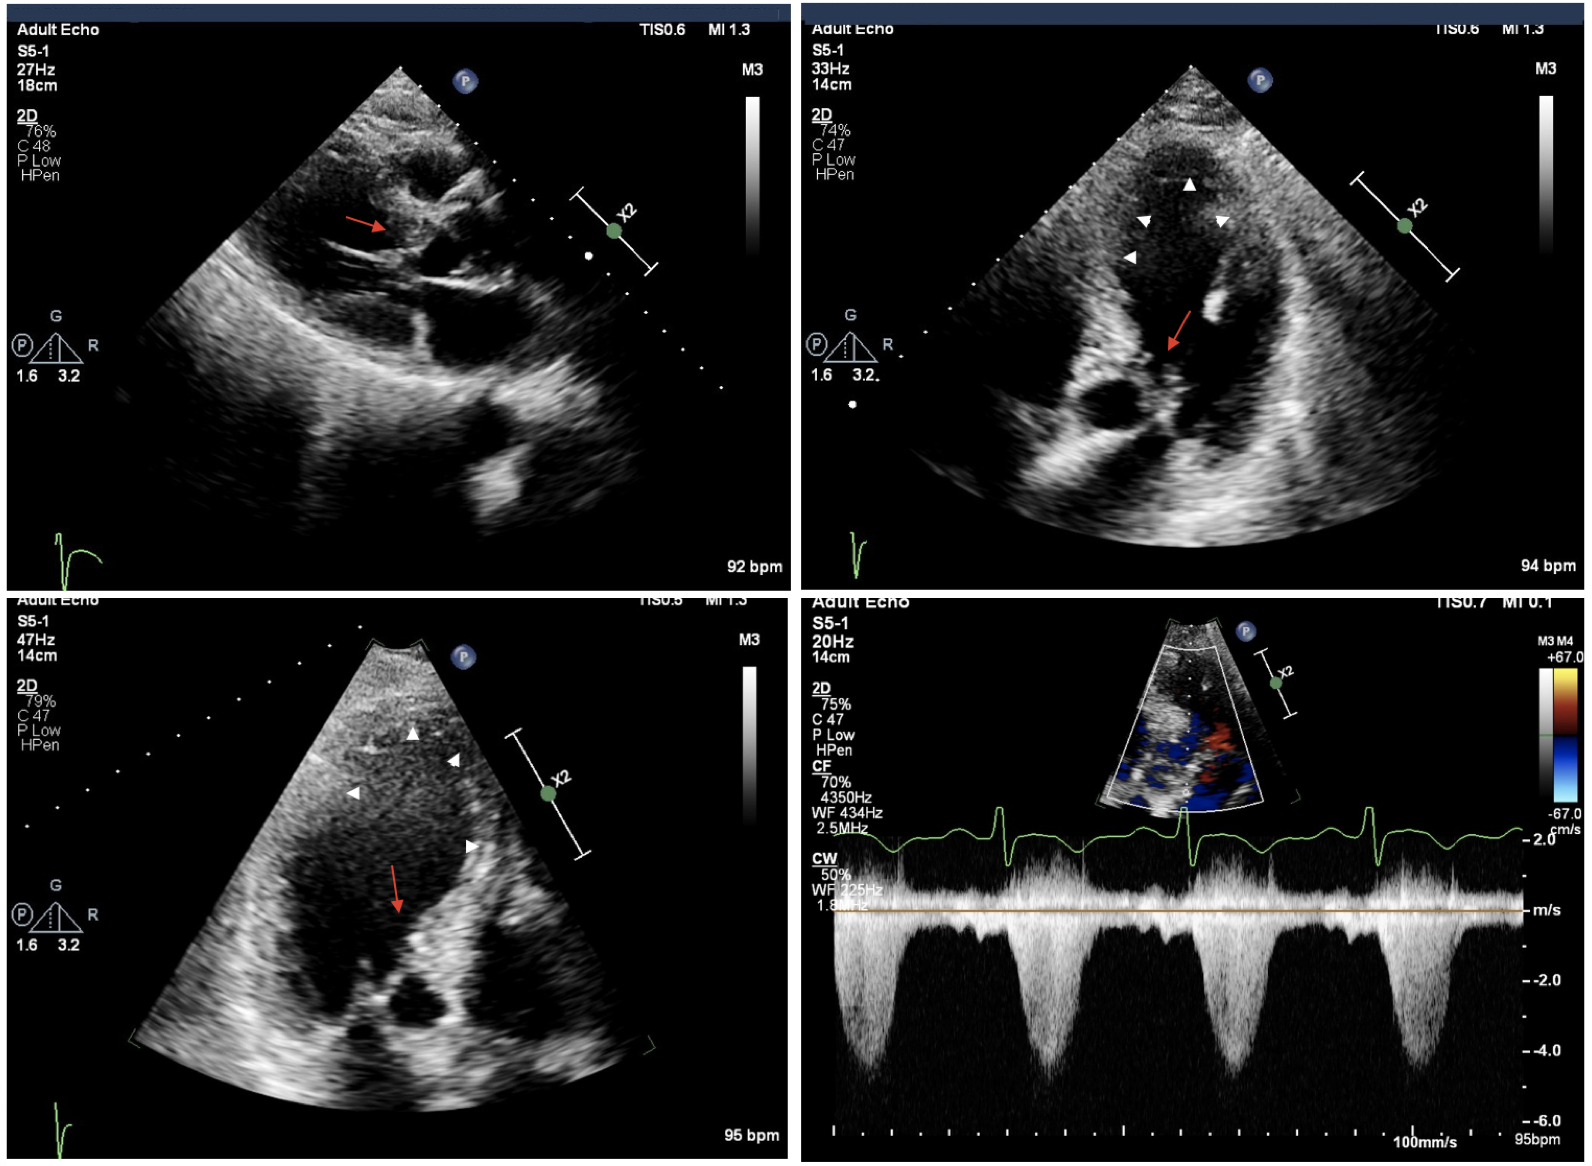

Dr. Harmony G. Reynolds and a research team are proving that OCT and cardiac MRI and can clarify why many women have heart attacks without coronary artery narrowing. Read the interview.